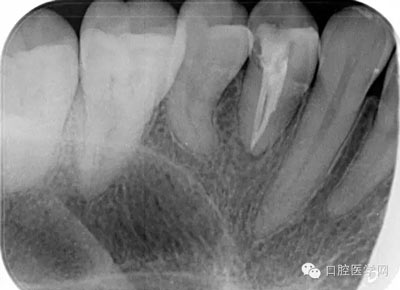

第七步:根管充填 使用對應(yīng)錐度及號數(shù)的牙膠尖充填。

第六步:運用S3鑷鈦系統(tǒng)進(jìn)行根管成形: 1S銼為04錐度20# 進(jìn)入根管口后啟動馬達(dá)。沿根管走向上下提拉3,4次。到達(dá)根管長度后,退出根管,大量5.25%次氯酸鈉沖洗。根尖有碎屑堆積時,可用15#不銹鋼K銼疏通根管。

2S銼為06錐度25# 在系統(tǒng)銼中如感到阻力可運用輕微的力以“啄”的手法運動。每次前進(jìn)1mm

直至工作長度。后退時以“刷”的手法進(jìn)行運動。每次預(yù)備完成,就要用大量5.25%次錄酸鈉沖洗。

3S銼為04錐度35# 鑷鈦根管銼在根管內(nèi)預(yù)備時停留時間不超過5秒,每次都應(yīng)該加入EDTA進(jìn)行根管潤滑,并每次退出根管銼時,都應(yīng)該用大量次氯酸鈉沖洗。